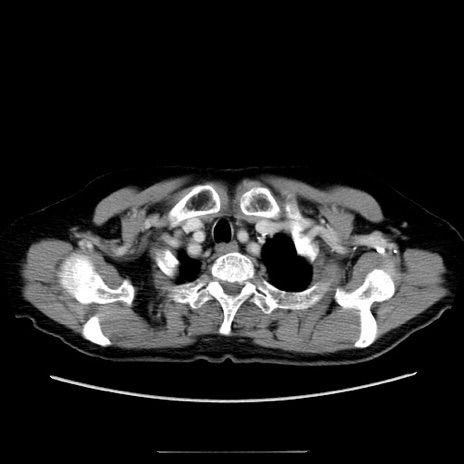

症例5(横断像)

【症例】70歳代女性

【主訴】お腹が張る

【現病歴】1週間くらい前から腹部膨満の自覚あり。昨日夜から増悪したため、本日救急外来受診。

【身体所見】意識清明、BT 36.5℃、BP 165/106mmHg、HR 80bpm、SpO2 98%、腹部:膨満、軟、自発痛・圧痛なし、触診にて不快感あり、腸蠕動音:減弱

【データ】WBC 12600、CRP 1.04